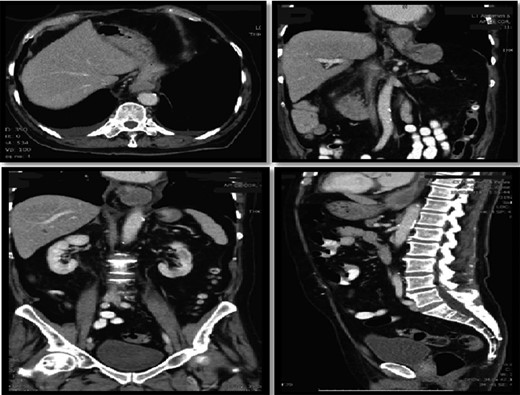

Interval gastroscopy in 2 weeks showed healing mucosal ischemia with slough from 27–30 cm (Fig. 3). Clear fluids were commenced and gradually upgraded to normal diet. Follow-up CT showed no contrast extravasation within posterior mediastinum (Fig. 4) and gastroscopy in 8 weeks showed healed esophagus.

Healing mucosal ischemia from upper, mid and distal esophagus.